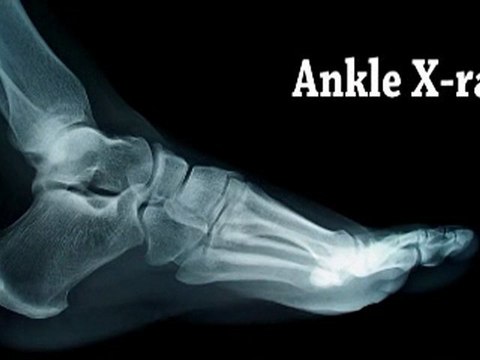

Foot and Ankle Surgery - Philadelphia, Norristown, PA - Podiatrist, Ankle and Foot Surgeon Dr. Kenneth D'Ortone of Center for Foot and Ankle Excellence discusses the symptoms, causes and treatments for Ankle Sprain. centerforfootandankle.com Surgery on the foot, ankle, or lower leg is usually performed by podiatric surgeons and orthopedic surgeons specializing in the foot and ankle. Foot and ankle surgeries address a wide variety of foot problems, including: • Sprains and fractures. • Arthritis and joint disease. • Benign and malignant tumors. • Birth deformities. • Bunions. • Calluses and warts. • Corns and hammertoes. • Flatfeet. • Heel or toe spurs. • Neuromas (nerve tumors). Many foot and ankle surgeries today can be performed in the doctor's office or a surgical center on an outpatient basis. They frequently can be performed using local anesthesia, in some cases combined with sedation. Most foot surgeries require a period of immob